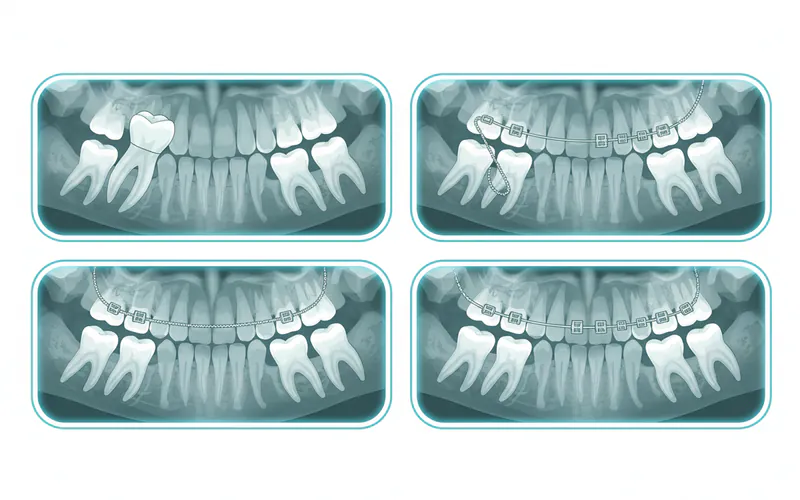

3. Surgical Exposure with Orthodontic Traction (Most Common)

- When: This is the primary treatment for most impacted canines that are good candidates for repositioning.

- Process:

- Surgical Exposure: An oral surgeon or periodontist surgically exposes the impacted canine.

- For palatal impactions, a small window of gum tissue is removed, and sometimes a tiny amount of bone, to reveal the crown. An orthodontic bracket with a small chain is then bonded directly to the exposed tooth. The gum tissue is then either sutured back around the bracket or left open.

- For buccal impactions, the tooth may be exposed, and the gum tissue trimmed to create a "window" for the tooth to erupt through (open eruption), or a bracket and chain are bonded, and the gum is closed over it (closed eruption).

- Orthodontic Traction: The attached chain is connected to the orthodontic archwire (braces). Over several months, the orthodontist applies gentle, continuous force to gradually pull the impacted canine into its correct position in the dental arch. This process is slow and controlled to avoid damaging the tooth or surrounding structures.

Step-by-Step Process for Surgical Exposure and Orthodontic Traction

This is the most common and detailed treatment for impacted canines. Here's what you can generally expect:

Step 1: Initial Consultation and Diagnosis

- Who: Orthodontist, General Dentist.

- What: Your orthodontist will perform a thorough clinical examination, reviewing your medical and dental history. Digital X-rays, including panoramic X-rays and potentially 3D cone-beam computed tomography (CBCT) scans, will be taken to precisely locate the impacted canine, assess its angulation, depth, and relationship to adjacent teeth and vital structures.

- Outcome: Confirmation of impaction, determination of its type (buccal or palatal), and initial treatment plan. This is also when your orthodontist may discuss types of teeth aligners or traditional braces that will be used for the traction and alignment phase.

Step 2: Pre-Surgical Orthodontic Preparation

- Who: Orthodontist.

- What: Before surgery, you will likely begin orthodontic treatment with braces or clear aligners. This phase is crucial for creating adequate space in the dental arch for the impacted canine to be pulled into. It may involve moving other teeth, expanding the arch, or removing crowded teeth if necessary.

- Duration: Typically 6-12 months.

Step 3: Surgical Exposure

- Who: Oral Surgeon or Periodontist.

- What: Once sufficient space is created, you will be referred to a specialist for the surgical procedure.

- Anesthesia: Local anesthesia will be administered to numb the area. Sedation options (e.g., nitrous oxide, oral sedation, or IV sedation) may also be offered for patient comfort.

- Incision: A small incision is made in the gum tissue over the anticipated location of the impacted tooth.

- Bone Removal (if necessary): If the tooth is covered by bone, a small amount of bone may be carefully removed to expose the crown.

- Attachment of Bracket: An orthodontic bracket with a small gold chain is carefully bonded to the exposed surface of the canine tooth.

- Closure/Open Eruption:

- Closed Eruption: For most palatal impactions, the gum tissue is gently repositioned and sutured back over the exposed tooth and bracket, leaving only the chain visible or tucked away. This protects the tooth during eruption.

- Open Eruption: For some buccal impactions, the gum tissue is trimmed to create a "window," leaving the tooth partially exposed to the oral cavity, which can allow for more rapid initial eruption.

- Duration: Approximately 45-90 minutes.

Step 4: Orthodontic Traction

- What: After the surgical site has healed (typically 1-2 weeks), you will return to your orthodontist.

- Activation: The orthodontist will attach the gold chain from the surgically exposed canine to the main archwire of your braces.

- Gentle Force: Very light, continuous forces are applied to gradually guide the impacted canine into its correct position. This usually involves adjustments to the chain or elastics during regular orthodontic appointments.

- Monitoring: Regular X-rays will be taken to monitor the tooth's movement and ensure it's progressing correctly.

- Duration: This phase can last anywhere from 6 to 18 months, depending on the severity of the impaction and the tooth's response.